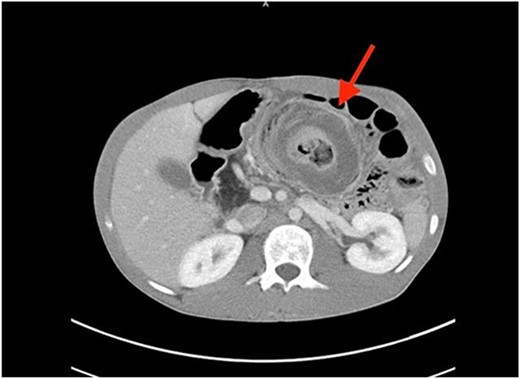

A coronal computed tomography (CT) scan with contrast showed a massive, small bowel to large bowel intussusception involving the majority of the ascending colon and portions of the cecum (Fig. 1). In addition, an axial CT scan showed the classic target sign associated with intussusception (Fig. 2). Due to the patient’s age, a pathologic lead point was suspected, hence surgery was consulted.

Axial CT scan showing characteristic target sign of bowel intussusception.